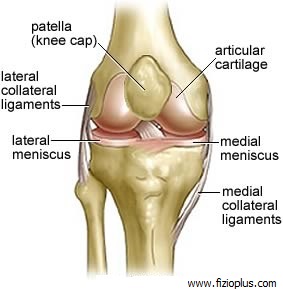

Paraqet një nga traumat më të shpeshta në sport dhe jetë. Zakonisht dëmtohet kompartmenti i jashtëm (80% të rasteve) pas traumës së përthyerjes së këmbës

Ligamenti kolateral medial (LKM) dhe ligamenti kolateral lateral (LKL) janë dy struktura të ngjitura nga kocka e femurit tek kocka e tibisë në anën e

Është sëmundja degenerative më e shpeshtë që kap artikulacionin e gjurit. Bëhet fjalë për një konsum të sipërfaqes artikulare të kockave që përbëjnë artikulacionin e